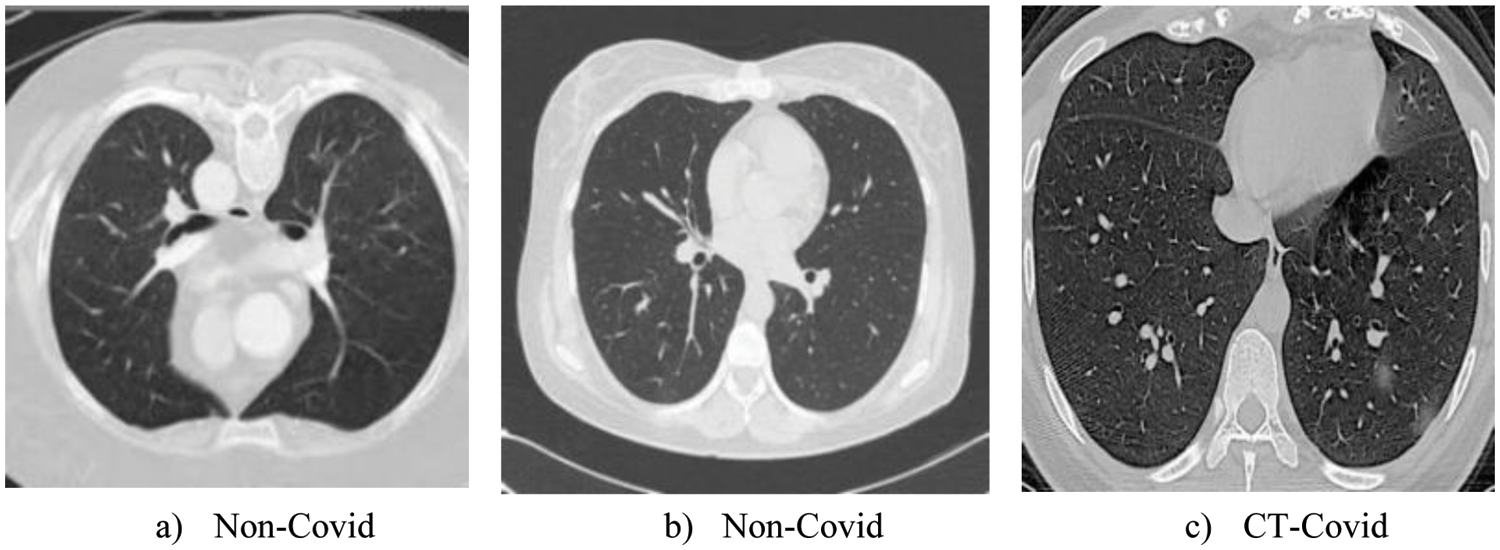

Computed tomography (CT) is very useful for the diagnosis of COVID-19. These days COVID is the biggest challenge all over the world, so for the evaluation of our proposed model COVID-CT dataset is used, which is an open-source publically available dataset [31,32]. The COVID-CT dataset is used by different researchers for the evaluation of deep learning models [33,34]. This dataset consists of 812 examples, of which 463 are non-covid examples, and 349 belong to covid images. These images are taken from 216 patients. This dataset is increased by performing an image augmentation method this way can train the neural network with high accuracy, so it helps to analyze the adversarial image performance. Some sample images of the dataset are shown in Fig. 4.

Figure 4: Sample images of CT-COVID dataset